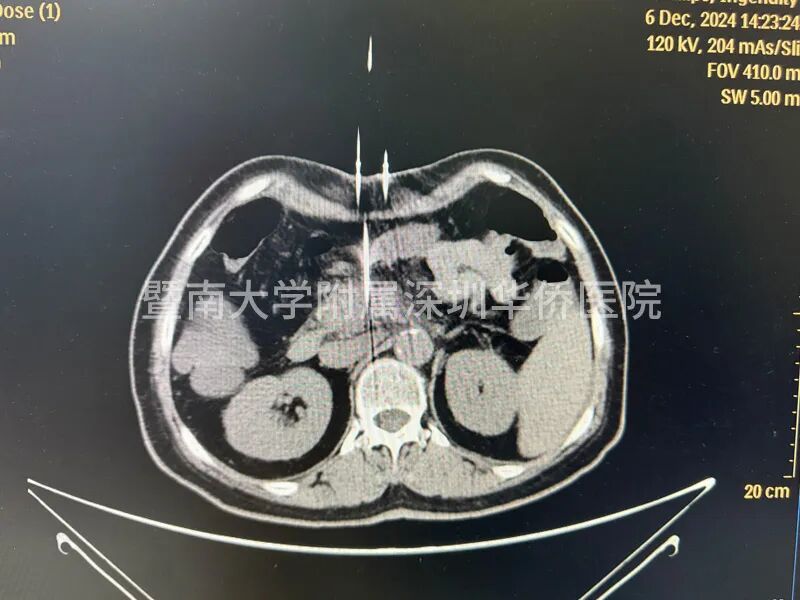

李女土的肿瘤在胰头位置,大小为2.8*3厘米,已经包绕肠系膜上动脉,失去了手术机会,在得知广东省应用了国产纳米刀治疗手术技术后,决定不远千里来到暨南大学附属深圳华侨医院,接受纳米刀消融手术。

上午11点,李女士正式进入手术室,多位相关领域专家,通过国产研发的新型设备正式对李女士进行手术,纳米刀消融技术适合中晚期的胰腺癌的治疗,这台手术设备在产品设计中,具有全球领先的核心技术,实现了在消融过程中,电压恰到好处,作用于细胞膜磷脂双分子层,形成不可逆电穿孔,诱导细胞凋亡,激活细胞免疫,经过几个小时的奋战,李女士成功完成手术治疗,此次纳米刀消融手术,顺利开展完成!

许林锋教授介绍:“纳米刀消融技术对操作者要求较高,与我们传统的消融手术也不同,以前的消融手术一个针就可以了,放到肿瘤的中心的部位,而纳米刀消融最少要有2根针,它是利用两个电极针之间的放电,就是一个公分的距离,可能有2-3千伏电压,所以说对电极针的定位非常重要。”

2、精准可控:在超声或CT引导下,纳米刀治疗系统能够精确计算出消融区域的形状和体积,并告知探针的有效消融范围。治疗计划精确到毫米级别,为患者提供个性化的治疗方案。

治疗效果:纳米刀治疗后,显微镜下可见治疗区域和非治疗区域界限清晰。直径大于一毫米的血管、主要血管和导管均不受影响,继续维持正常功能。治疗后1-3个月,通过CT扫描几乎看不到治疗痕迹。